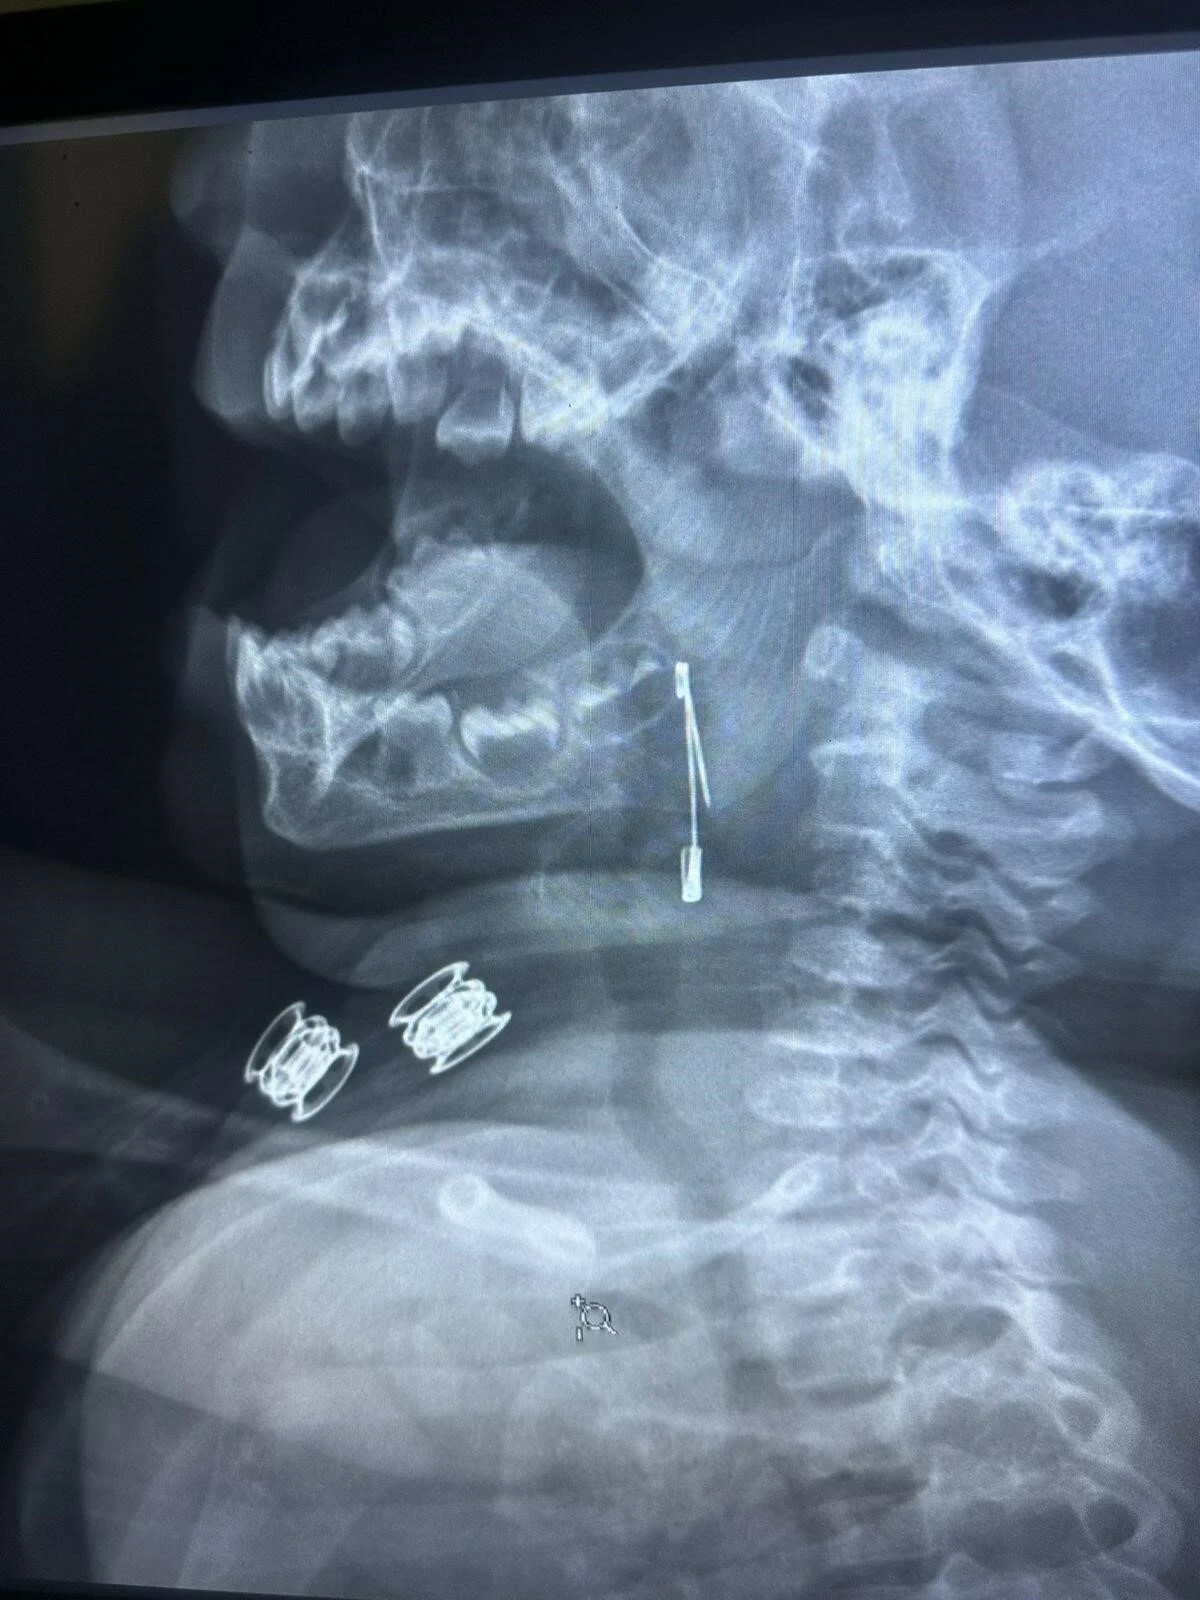

Bitlis’in Güroymak ilçesinde, soluk borusuna çengelli iğne kaçan 8 aylık bebek, yapılan başarılı bir operasyonla sağlığına kavuştu.

Güroymak ilçesinde 8 aylık bebek, evde bulunan çengelli iğneyle oynarken onu yuttu. Öksürmeye başlayan minik çocuğun, hastanede çekilen röntgen sonucu çengelli iğneyi yuttuğu fark edildi. Güroymak Devlet Hastanesi’nden Tatvan Devlet Hastanesi’ne ambulansla sevki gerçekleşen minik çocuk, Kulak Burun Boğaz Hastalıkları Uzmanı Operatör Dr. Hakan Tuhan tarafından yapılan başarılı operasyonla sağlığına kavuştu. Çengelli iğnenin saplı olduğu soluk borusundan çıkarılan bebek, 2 saatlik gözlemin ardından taburcu edildi.

Konuyla ilgili açıklamada bulunan Kulak Burun Boğaz Hastalıkları Uzmanı Operatör Dr. Hakan Tuhan, “8 aylık bir bebek, Bitlis’in Güroymak ilçesinden tarafımıza danışıldı. Güroymak ilçesinde çekilen röntgen sonucunda çengelli iğnenin soluk borusunun girişinde olduğunu teyit ettik. Yapılan müdahaleler sonucunda çengelli iğneyi çıkardık. Çıkardıktan sonra iki saat kadar gözlem altında tuttuk hastamızı. Daha sonrasında herhangi bir komplikasyonla karşılaşmadık ve sorunsuz bir şekilde taburcu ettik” dedi.